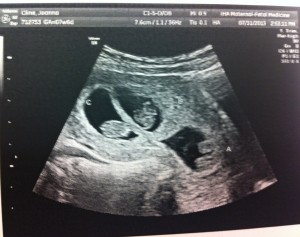

Good morning! I’m 10w1d today and we went for another ultrasound this morning. The u/s tech told us that everything looks exactly as she’d want it to at this point in the pregnancy. The heartbeats are great and they are wiggling around in there!

I’ve attached a few new photos – close ups of each and one group shot. 🙂